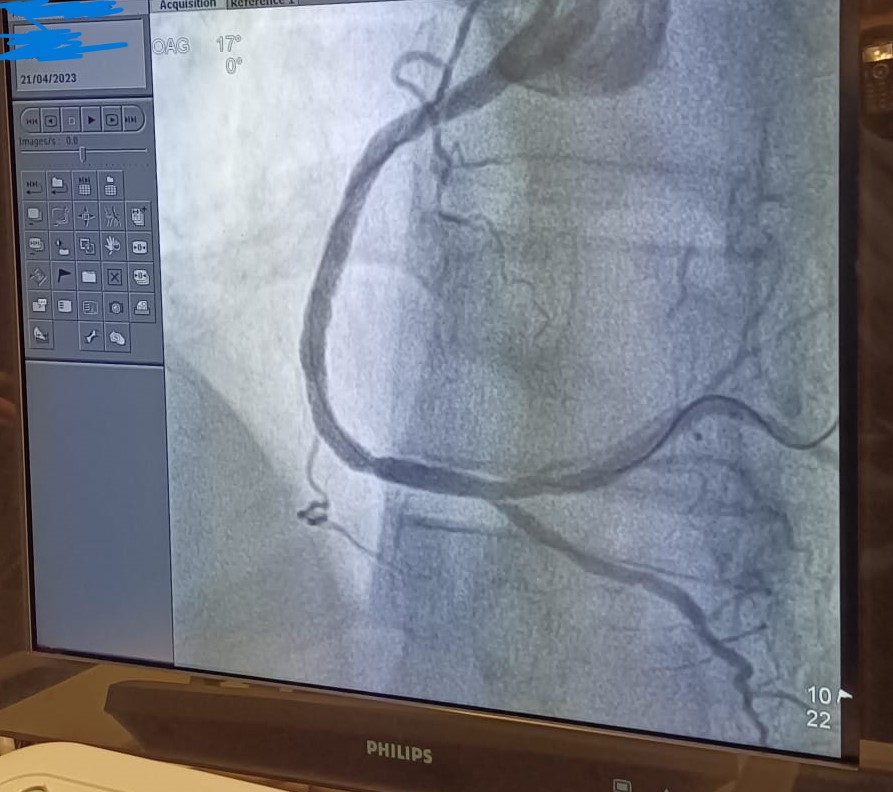

Unsurprisingly, an occluded RCA, featuring multilevel lesions.

Both the thrombo-aspiration and the angioplasty are successfull.

(The LCA is not unscathed, and will probably need a deferred intervention).